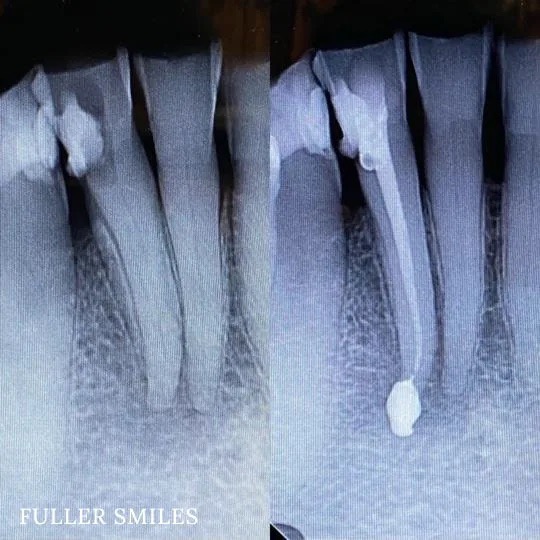

Patient presented with a complaint of severe constant pain that would exaggerate on laying down and biting. Patient wanted to save the tooth. A thorough clinical exam, endodontic screening and proper x rays led to the diagnosis of necrotic (dead) pulp due to dental caries with inflamed periodontal ligaments.

Our Dentists used the latest technology and highest quality products to finish this beautiful root canal. The tooth was crowned after the root canal to restore function and aesthetics.